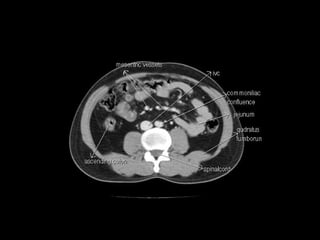

Radiographers use medical imaging equipment like X-rays and MRIs to produce images of patients' internal structures and organs. They are responsible for positioning patients, operating scanning machines, and ensuring quality images. Radiographers must have strong attention to detail, excellent communication skills, and the ability to work well under pressure to accurately capture anatomical features and diagnose any abnormalities.